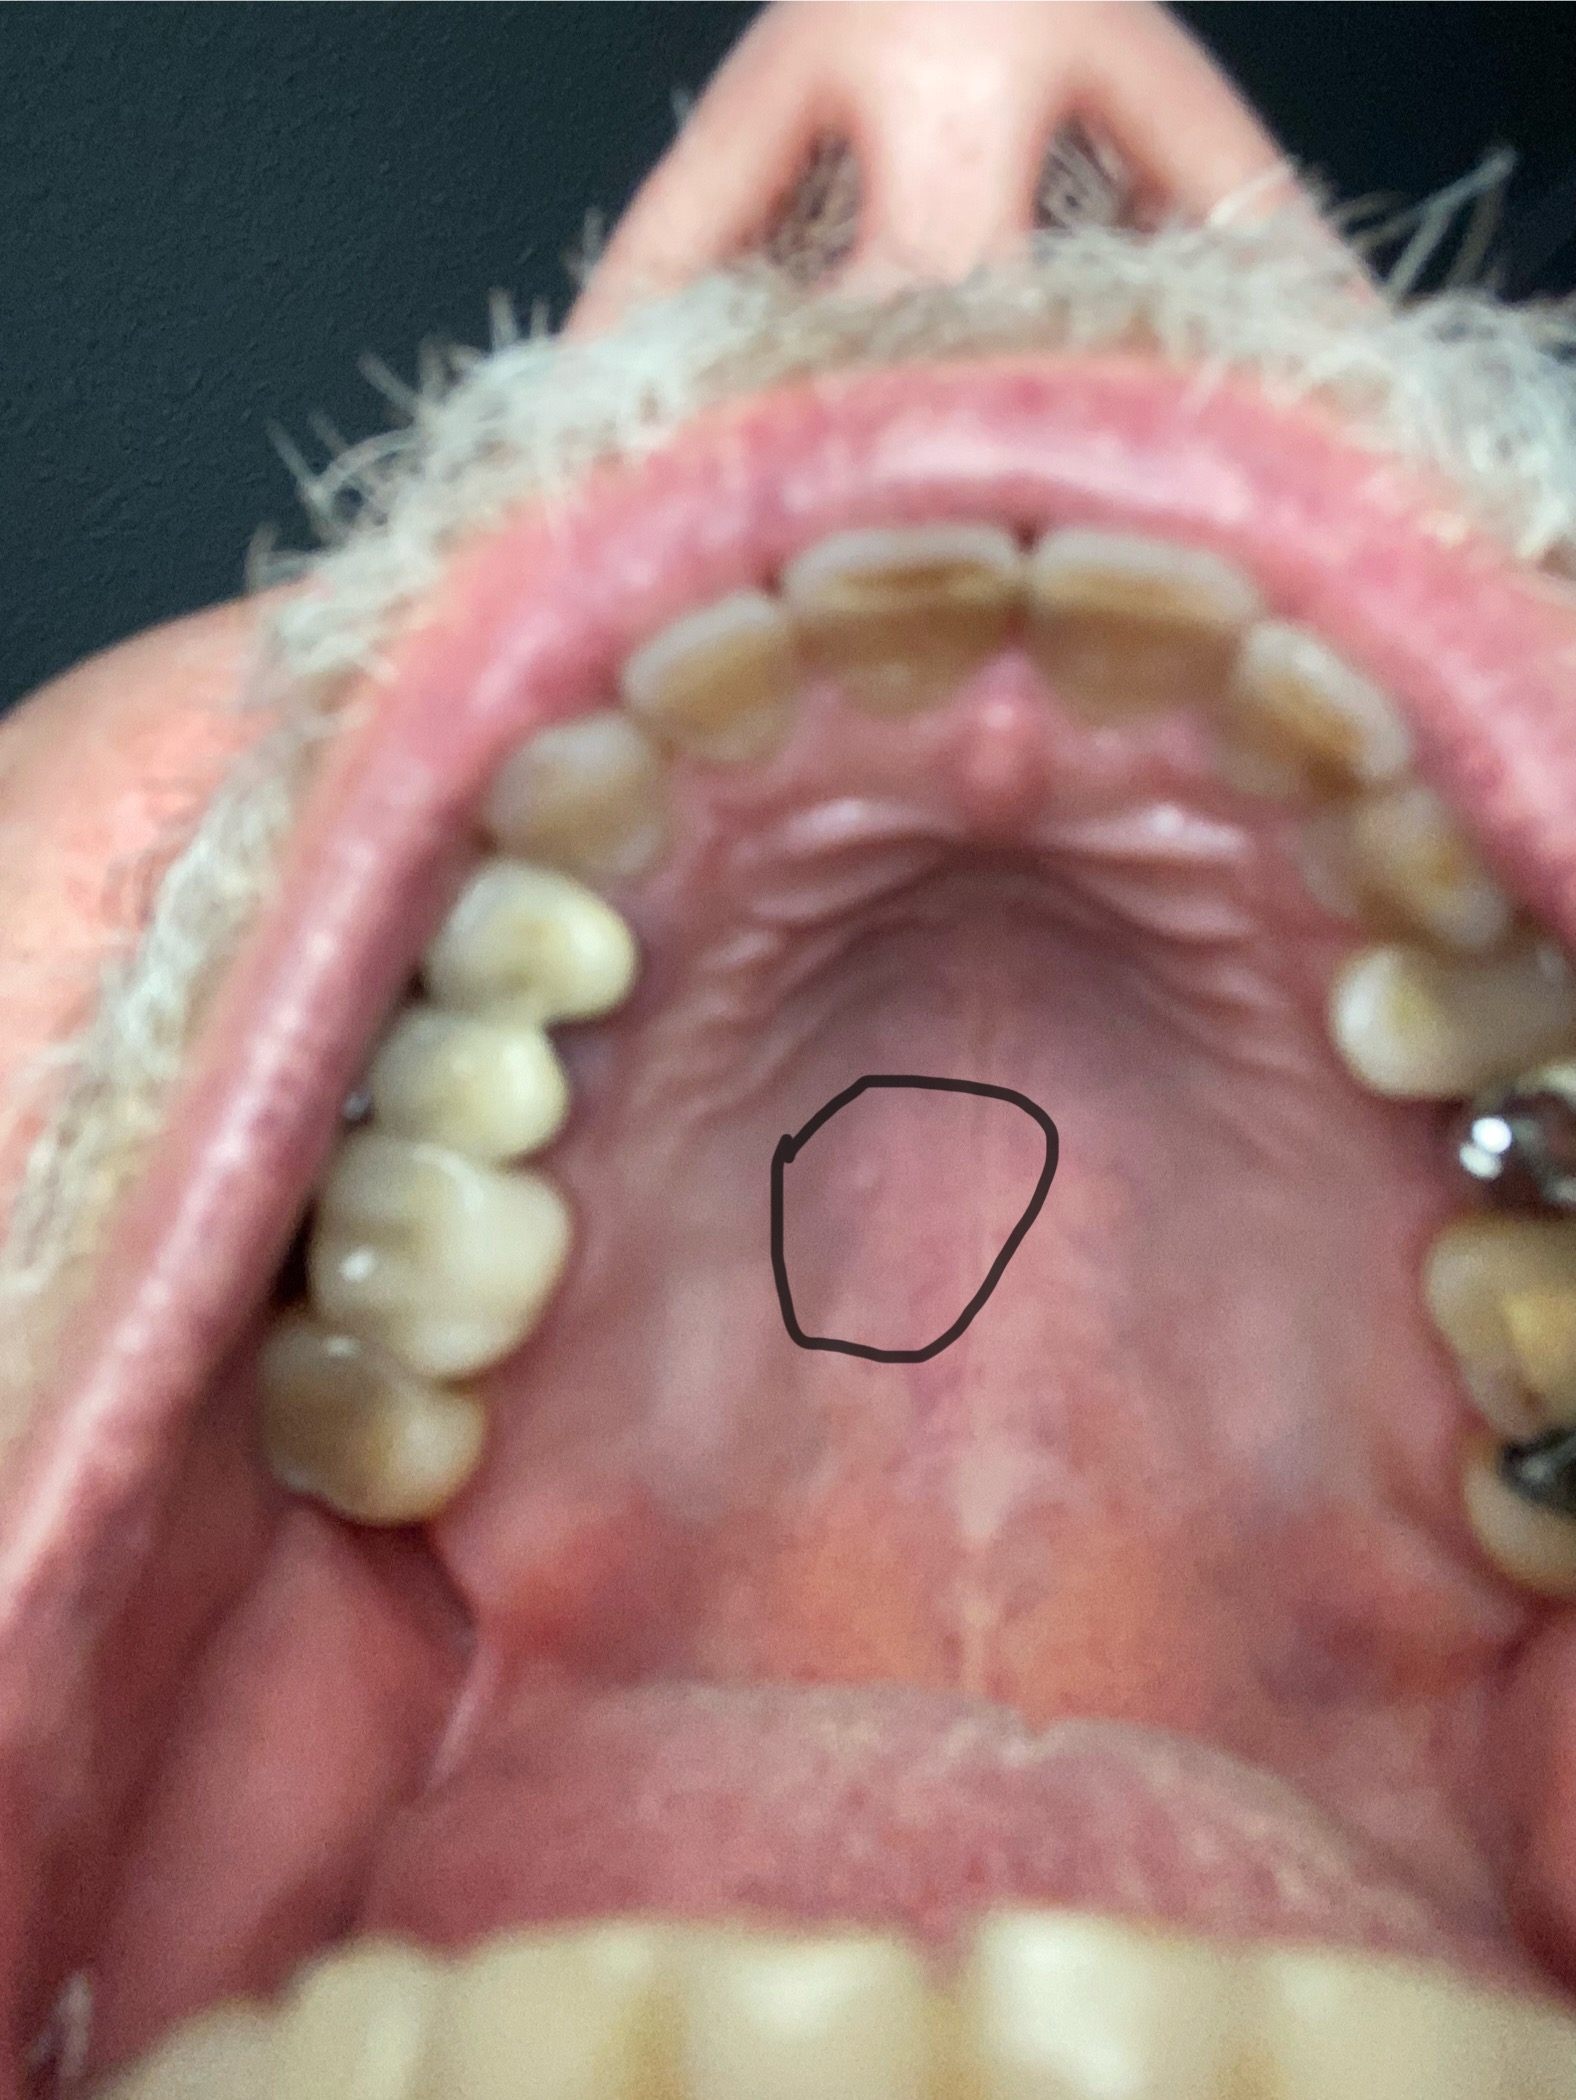

seit mehren Jahren habe ich am Gaumen eine Erhebung wie einen kleinen Pickel. Er tut nicht weh, sieht auch wie normale Schleimhaut aus. Ich bin halt immer mit der Zunge dran. Ich habe das Gefühl, das sich die Größe im Tagesverlauf geringfügig ändert. Muss das operativ entfernt werden? Oder ist das nichts Schlimmes, kann verbleiben. Vielleicht eine vergrößerte Speicheldrüse?

Vielen Dank Herr Dr. Belsky. Ich wollte Sie nicht stören. Ich hatte nur gefragt, weil ich die Veränderung schon viele Jahre bemerke. Wenn das in Ordnung ist, bin ich beruhigt. Ich hatte ähnliche Bilder gesehen, wo aber von vorübergehenden Dingen geschrieben wurde. Herzliche Grüße und alles Gute fürs neue Jahr Burkhard Weber